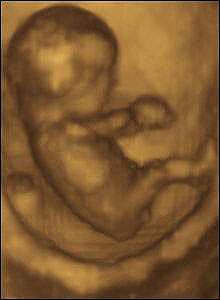

•   超声波检验(即为B超)原本是怀孕妇女的惯例检验之一,现在在美国等地,却兴起了用超声波扫描器给腹中母体的幼体拍写真集高潮美国全国各大购物中心都冒出了一些名为“母体的幼体摄影”、“产前拍摄”和“看看子宫”的连锁工作室,为准父母提早看到可爱宝宝供给服务。不过,如此做对母体的幼体平安吗? www.bbcms.net转载自网络

据6月14日出版的美国《人物》杂志报道,在美国为母体的幼体拍写真的收费在50美元-300美元之间,拍出的母体的幼体照片非常明晰,能够看到母体的幼体的表情,还能数清母体的幼体的手指和脚趾。

自20世纪60年月以来,超声波检验已成为产前怀孕的妇女例行检验的一个重要环节。它利用超声波的物理特征和人体组织构造的声学特色,将母体的幼体的影像显示在监督屏上,实行动态察看,可替早期怀怀孕的妇女女评价受孕周数、诊断治疗早期受孕异常、诊断治疗多胞胎、检测出子宫及卵巢异常、评价母体的幼体发育情况等。